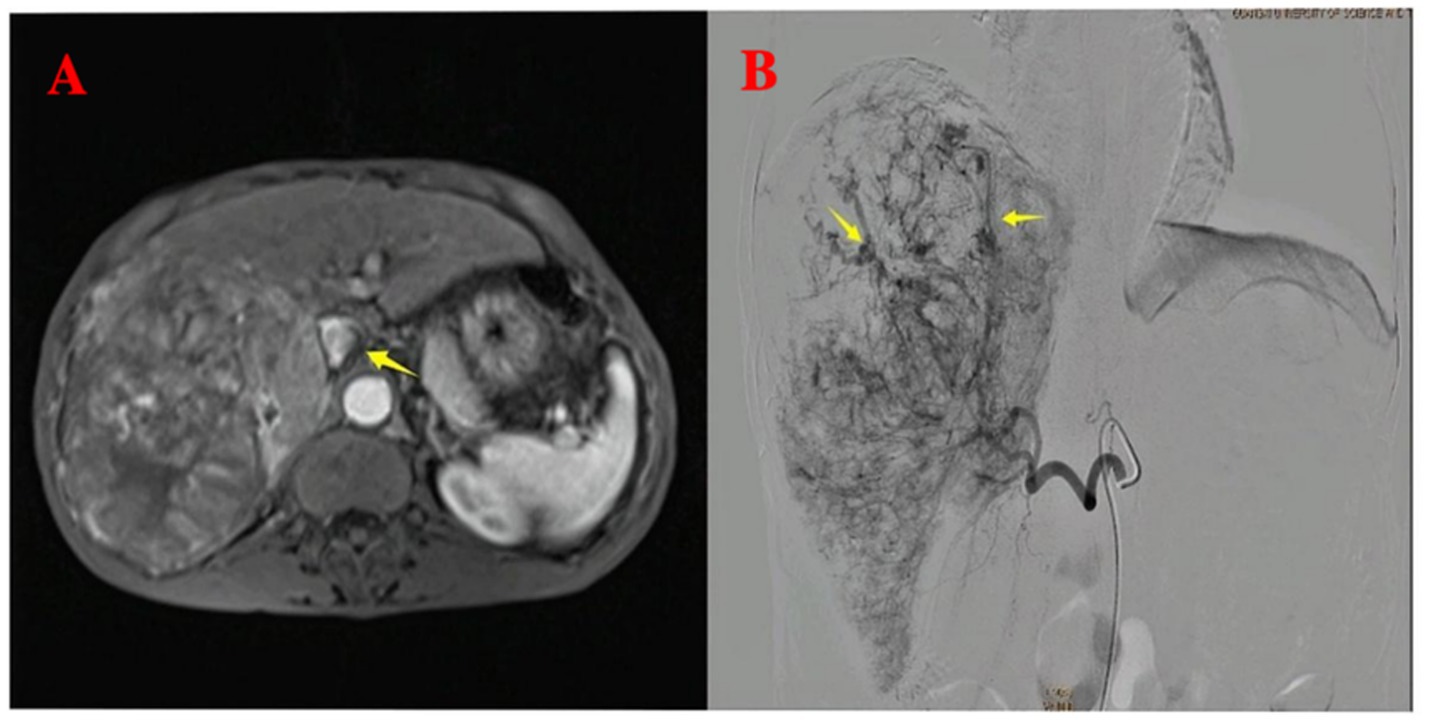

A 64-year-old male patient with multiple HCCs and portal vein invasion (Figure 1A) was classified as Child–Pugh B. Preoperative tumor markers showed an alpha-fetoprotein (AFP) level of 12,263.96 ng/mL (reference range: <10.0 ng/mL) and carcinoembryonic antigen (CEA) of 16.4 ng/mL (reference range: <10.0 ng/mL). Laboratory tests revealed a white blood cell count of 9.43 × 109/L (reference range: 4.0–10.0 × 109/L) and platelet count of 195 × 109/L (reference range: 100–300 × 109/L). Liver function tests showed albumin 32.7 g/L (reference range: 40–55 g/L), aspartate aminotransferase (AST) 843.6 U/L (reference range: 15–40 U/L), alanine aminotransferase (ALT) 238.8 U/L (reference range: 9–50 U/L), total bilirubin (TBIL) 34.8 μmol/L (reference range: 0–26 μmol/L), direct bilirubin (DBIL) 14.90 μmol/L (reference range: 0–6.8 μmol/L), and indirect bilirubin (IBIL) 19.9 μmol/L (reference range: 0–17.0 μmol/L). Renal function was normal. Transthoracic echocardiography revealed no atrial septal defect or other intracardiac shunts. The patient underwent the first TACE. Given the tumor’s diameter exceeding 130 mm, the procedure was performed under close monitoring to ensure no reflux of lipiodol. A total of 40 mL of lipiodol, 2 mg of raltitrexed, and 20 mg of lobaplatin were infused. Due to the patient’s family’s limited financial resources and refusal to use coil embolization, gelatin sponge particles (560–710 μm) were used to block the vessels. Following embolization, hepatic arteriography was repeated, confirming the successful closure of the arteriovenous fistula, after which the tumor was embolized with lipiodol. Intraoperative angiography demonstrated an arterioportal shunt (Figure 1B). Twenty hours postoperatively, the patient developed decreased consciousness and right-sided weakness with numbness, without headache or visual disturbances. Physical examination revealed blood pressure of 116/75 mmHg (1 mmHg = 0.133 kPa), with normal pulse, respiratory rate, and body temperature. Neurological examination showed a clear mental status with appropriate responses, right nasolabial fold flattening, midline tongue protrusion, right upper limb muscle strength grade 2, other limbs grade 5, decreased superficial sensation on the right side, and positive Babinski sign on the right; no other pathological signs were noted. Head CT performed 20 h and 30 min postoperatively revealed multiple abnormal density lesions in the bilateral cerebral cortex, subcortical regions, basal ganglia, thalami, and periventricular areas (Figures 2A,B). MRI performed 24 h postoperatively, including diffusion-weighted imaging (DWI), showed scattered punctate and patchy hyperintense or slightly hyperintense lesions in the bilateral frontal, temporal, parietal, and occipital lobes as well as the basal ganglia, with poorly defined margins (Figures 2C,D). Neurology consultation suggested cerebral embolism secondary to iodized oil. The patient’s consciousness gradually improved over the following week; however, right-sided weakness persisted without significant recovery. The patient remains under follow-up.

Figure 1

Pre-procedural imaging and intra-procedural angiographic findings. (A) Pre-procedural axial T1-weighted contrast-enhanced imaging reveals multiple hepatocellular carcinoma lesions with portal vein invasion (yellow arrow). (B) Intra-procedural digital subtraction angiography during the first TACE demonstrates arteriovenous shunting.